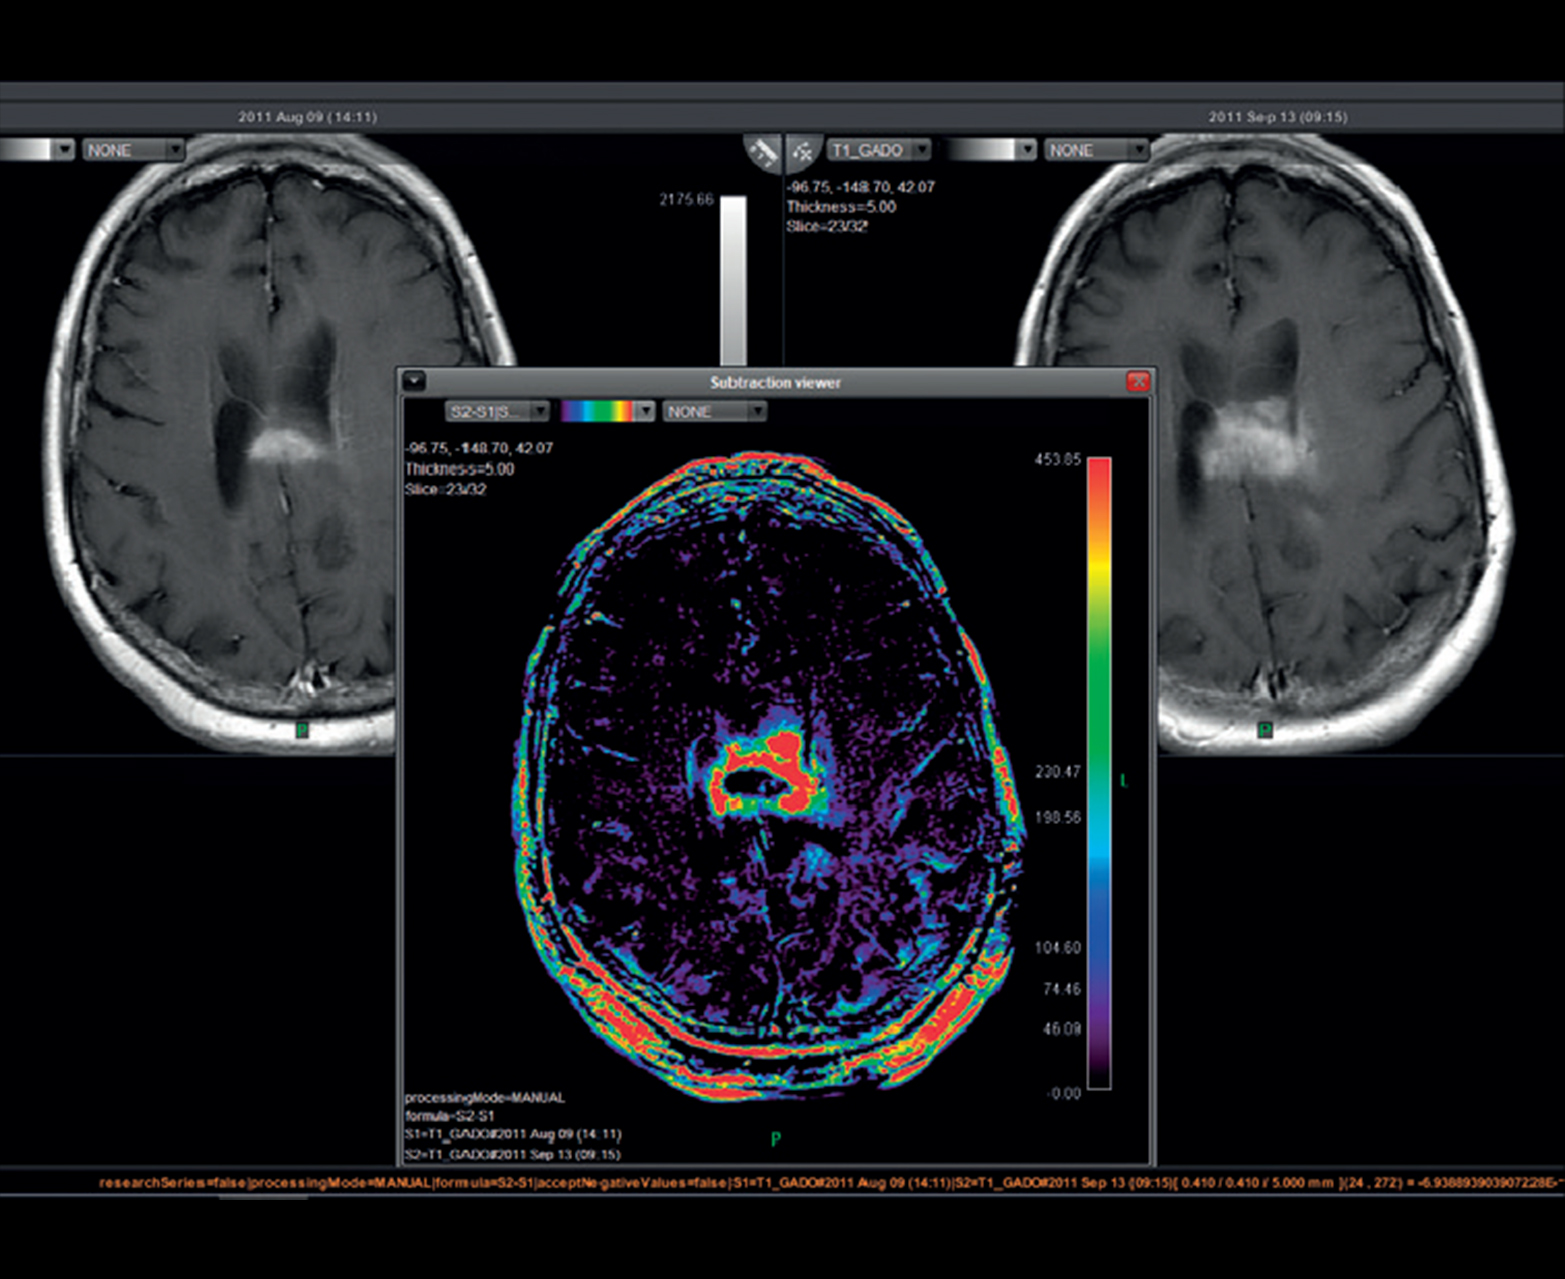

• Последующее наблюдение за развитием поражения и анализ ответа на лечение с временным вычитанием

Последующее наблюдение за поражением с совместной регистрацией